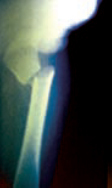

Vous pratiquez une radiographie du membre inférieur droit. Elle montre une fracture transversale du col du fémur.

Figure.